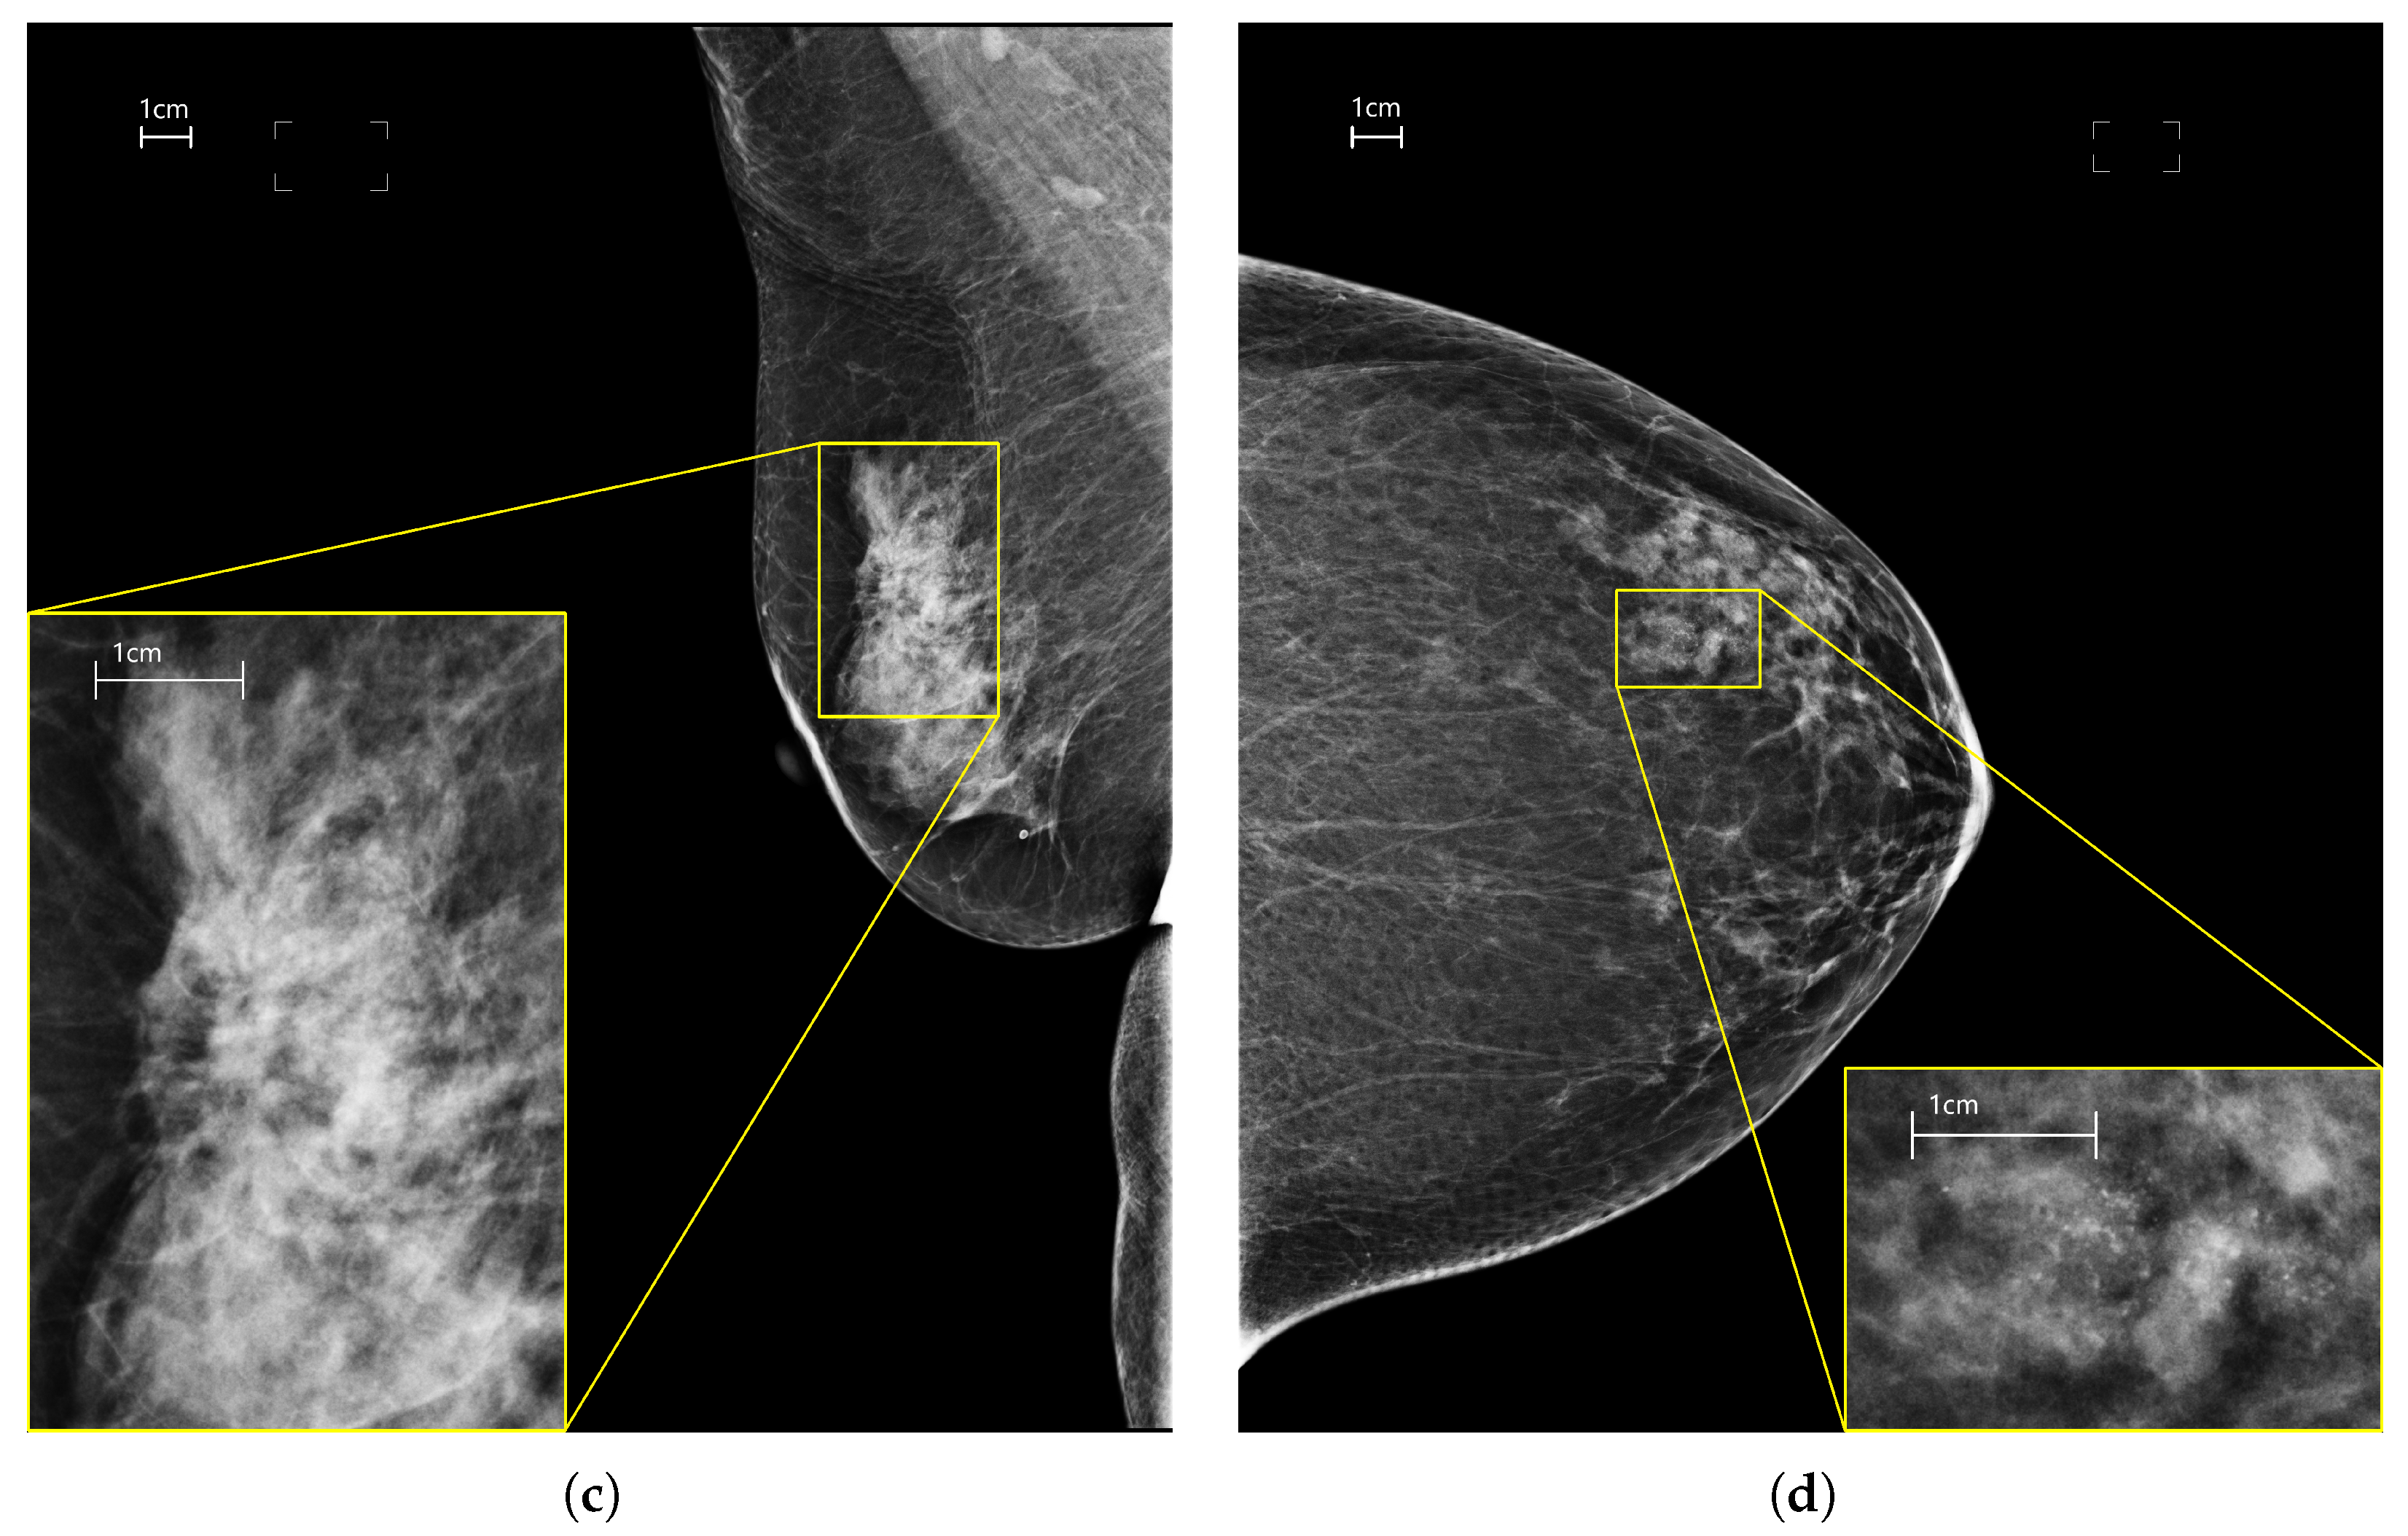

2.1. Dataset

- Positive class: containing 5801 images with malignant findings selected from cases classified as malignant by either surgery, or biopsy, or previously classified as malignant. Each image may contain one or more of the following lesions: masses, calcifications, architectural distortions, focal asymmetries;

- Negative class: composed of 9895 images from women with normal breast.